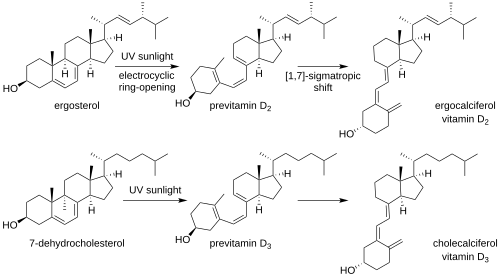

Biosynthesis

Synthesis of vitamin D in nature is dependent on the presence of UV radiation and subsequent activation in the liver and the kidneys. Many animals synthesize vitamin D3 from 7-dehydrocholesterol, and many fungi synthesize vitamin D2 from ergosterol.[47]

Vitamin D3 is produced photochemically from 7-dehydrocholesterol in the skin of most vertebrate animals, including humans.[180] The skin consists of two primary layers: the inner layer called the dermis, and the outer, thinner epidermis. Vitamin D is produced in the keratinocytes of two innermost strata of the epidermis, the stratum basale and stratum spinosum, which also can produce calcitriol and express the vitamin D receptor.[181] The 7-dehydrocholesterol reacts with UVB light at wavelengths of 290–315 nm. These wavelengths are present in sunlight, as well as in the light emitted by the UV lamps in tanning beds (which produce ultraviolet primarily in the UVA spectrum, but typically produce 4% to 10% of the total UV emissions as UVB). Exposure to light through windows is insufficient because glass almost completely blocks UVB light.[182] In skin, either permanently in dark skin or temporarily due to tanning, melanin is located in the stratum basale, where it blocks UVB light and thus inhibits vitamin D synthesis.[49]

The transformation in the skin that converts 7-dehydrocholesterol to vitamin D3 occurs in two steps. First, 7-dehydrocholesterol is photolyzed by ultraviolet light in a 6-electron conrotatory ring-opening electrocyclic reaction; the product is previtamin D3. Second, previtamin D3 spontaneously isomerizes to vitamin D3 (cholecalciferol) via a [1,7]-sigmatropic hydrogen shift. In fungi, the conversion from ergosterol to vitamin D2 follows a similar procedure, forming previtamin D2 by UVB photolysis, which isomerizes to vitamin D2 (ergocalciferol).[4]